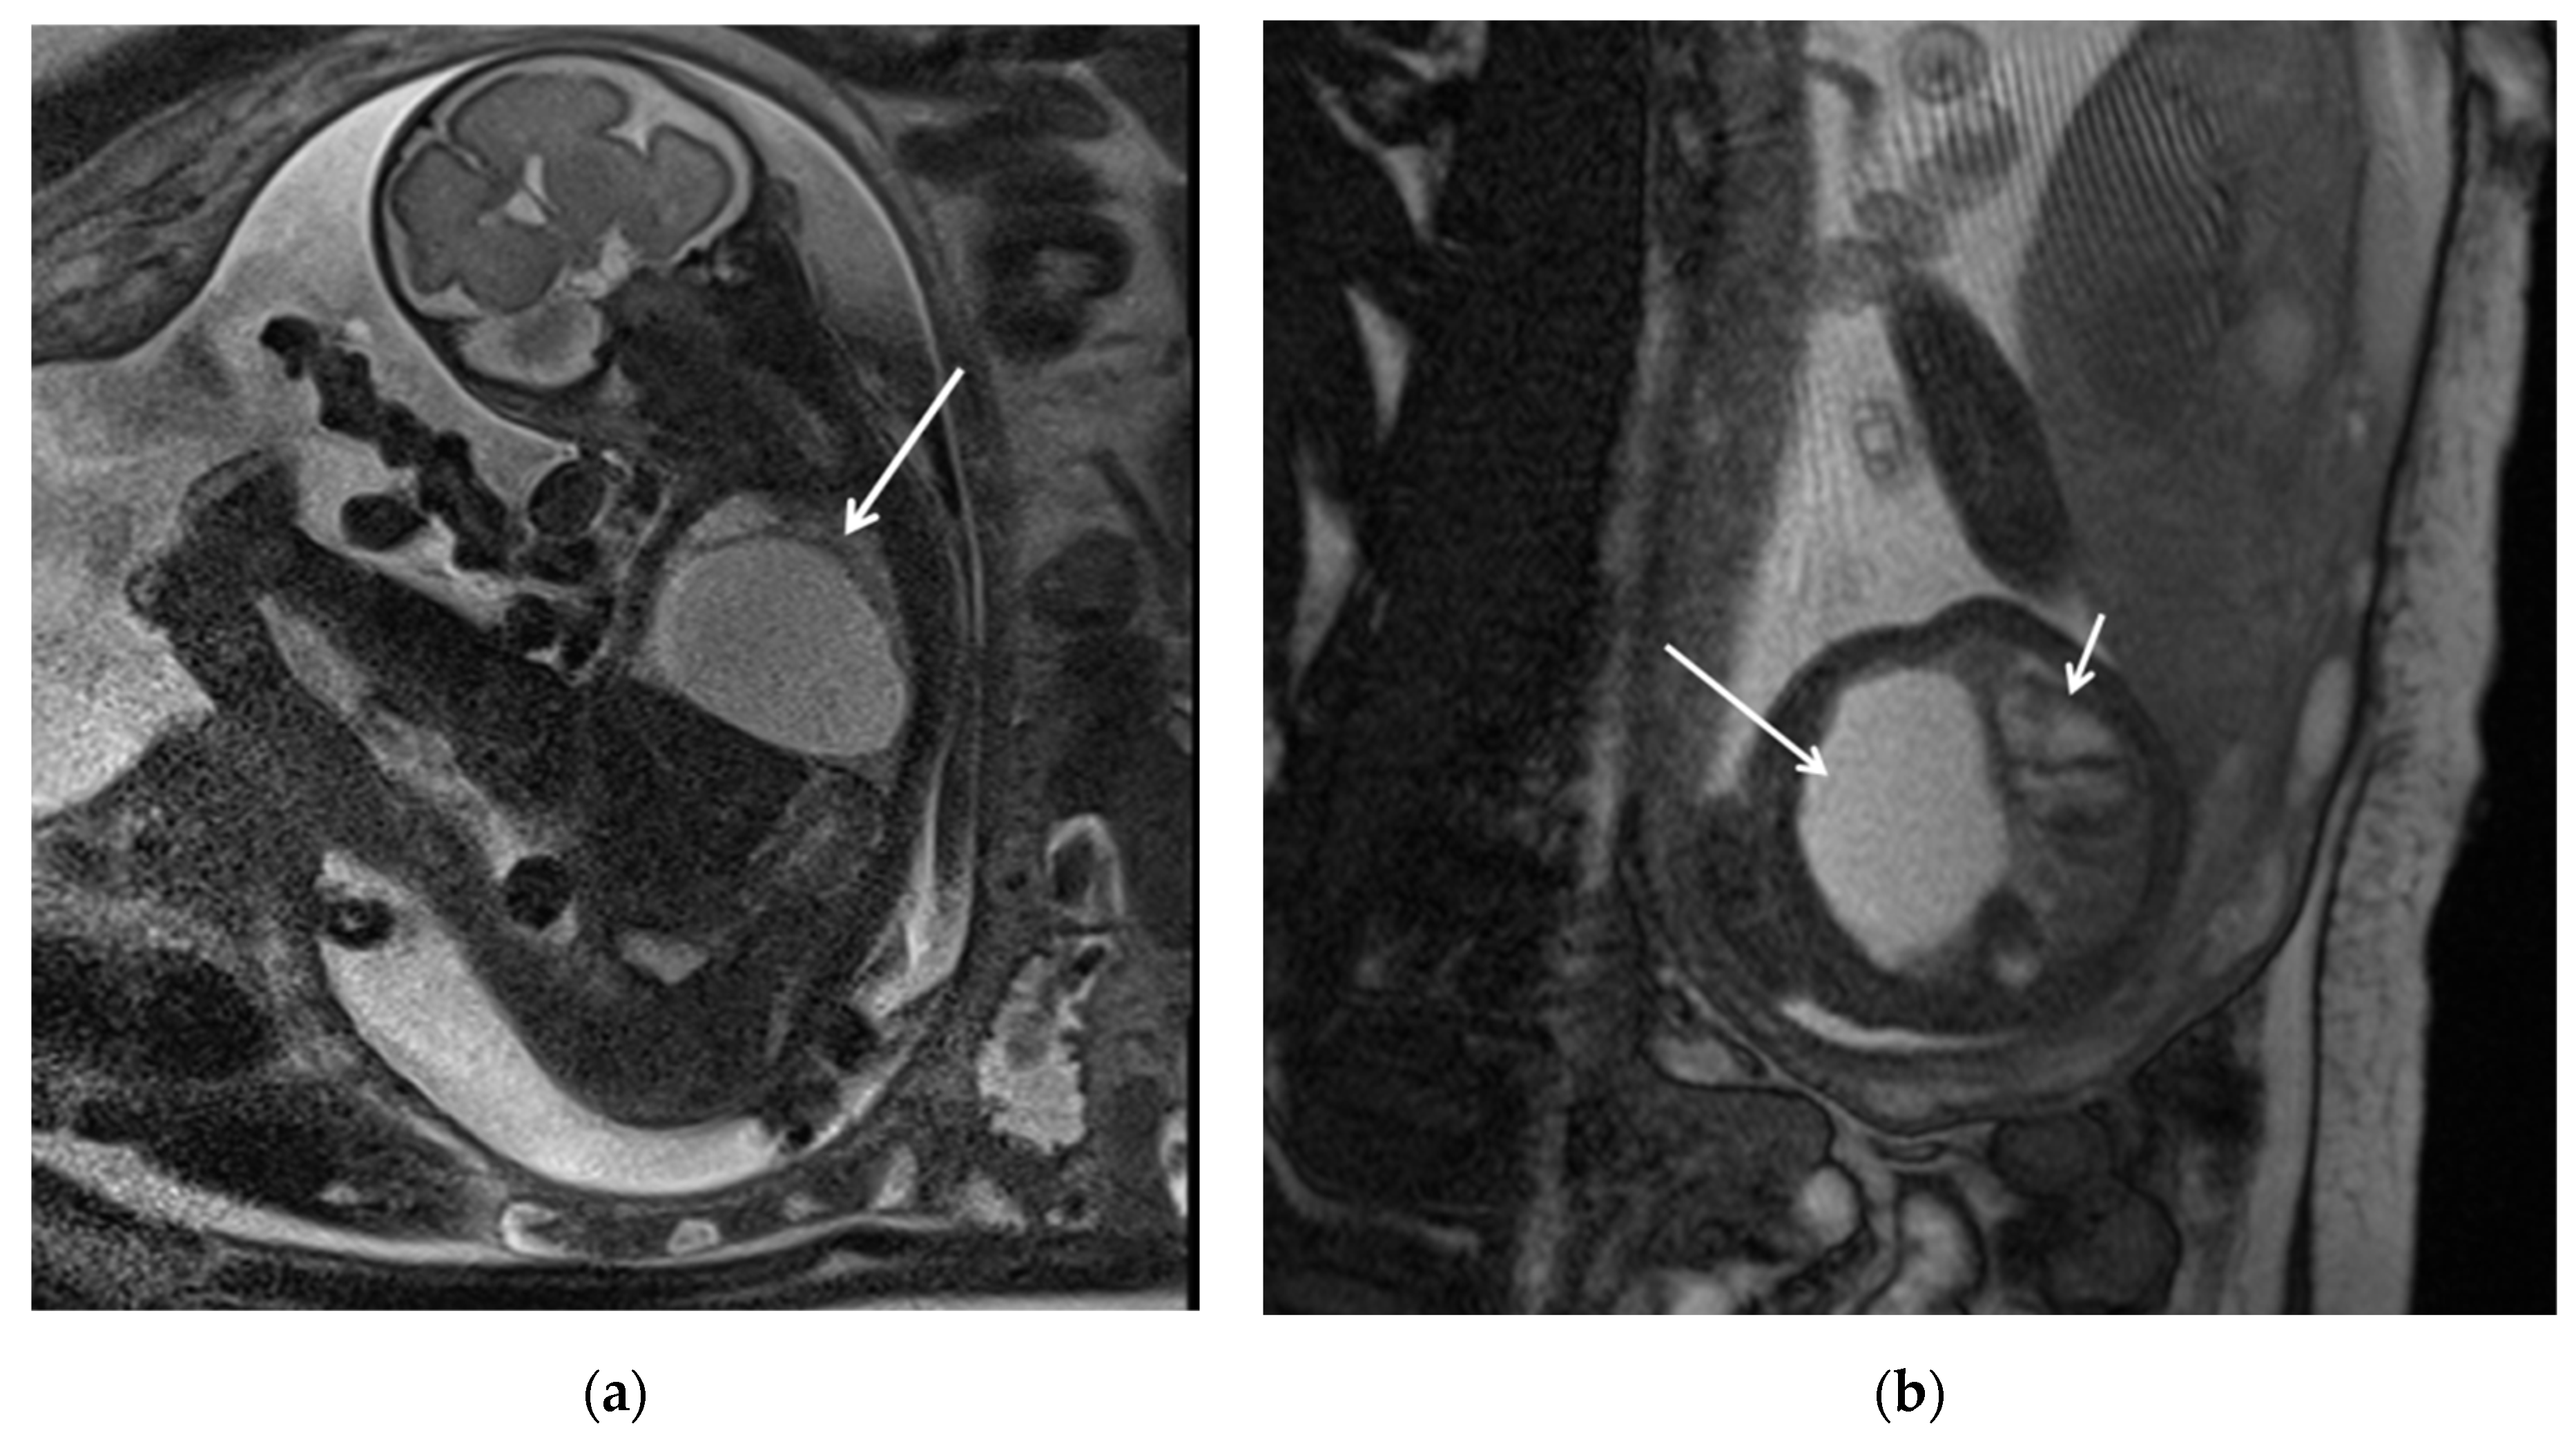

Congenital pulmonary airway malformations (CPAM) are subdivided into five types (0–4), with each type characterized by distinct features: Type 0 involves the trachea and mainstem bronchi and is lethal postnatally; Type I affects the bronchi and proximal bronchioles and is associated with large cysts (Figure 1); Type II involves the bronchiolar area with smaller cysts (less than 2 cm) (Figure 2); Type III affects the bronchiolar/alveolar duct region, often appearing as homogeneous hypodense masses on CT (Figure 3); and Type IV involves the alveolar/saccular region, causing unlined cysts [8].

Figure 1. CPAM type I. HASTE oblique sagittal (a) and True FISP (b) MRI scans taken at 28 weeks of gestation reveal a large fluid-filled mass with bright T2 signal in the right chest (arrows). This abnormality results in a shift of the heart toward the left side of the mediastinum.